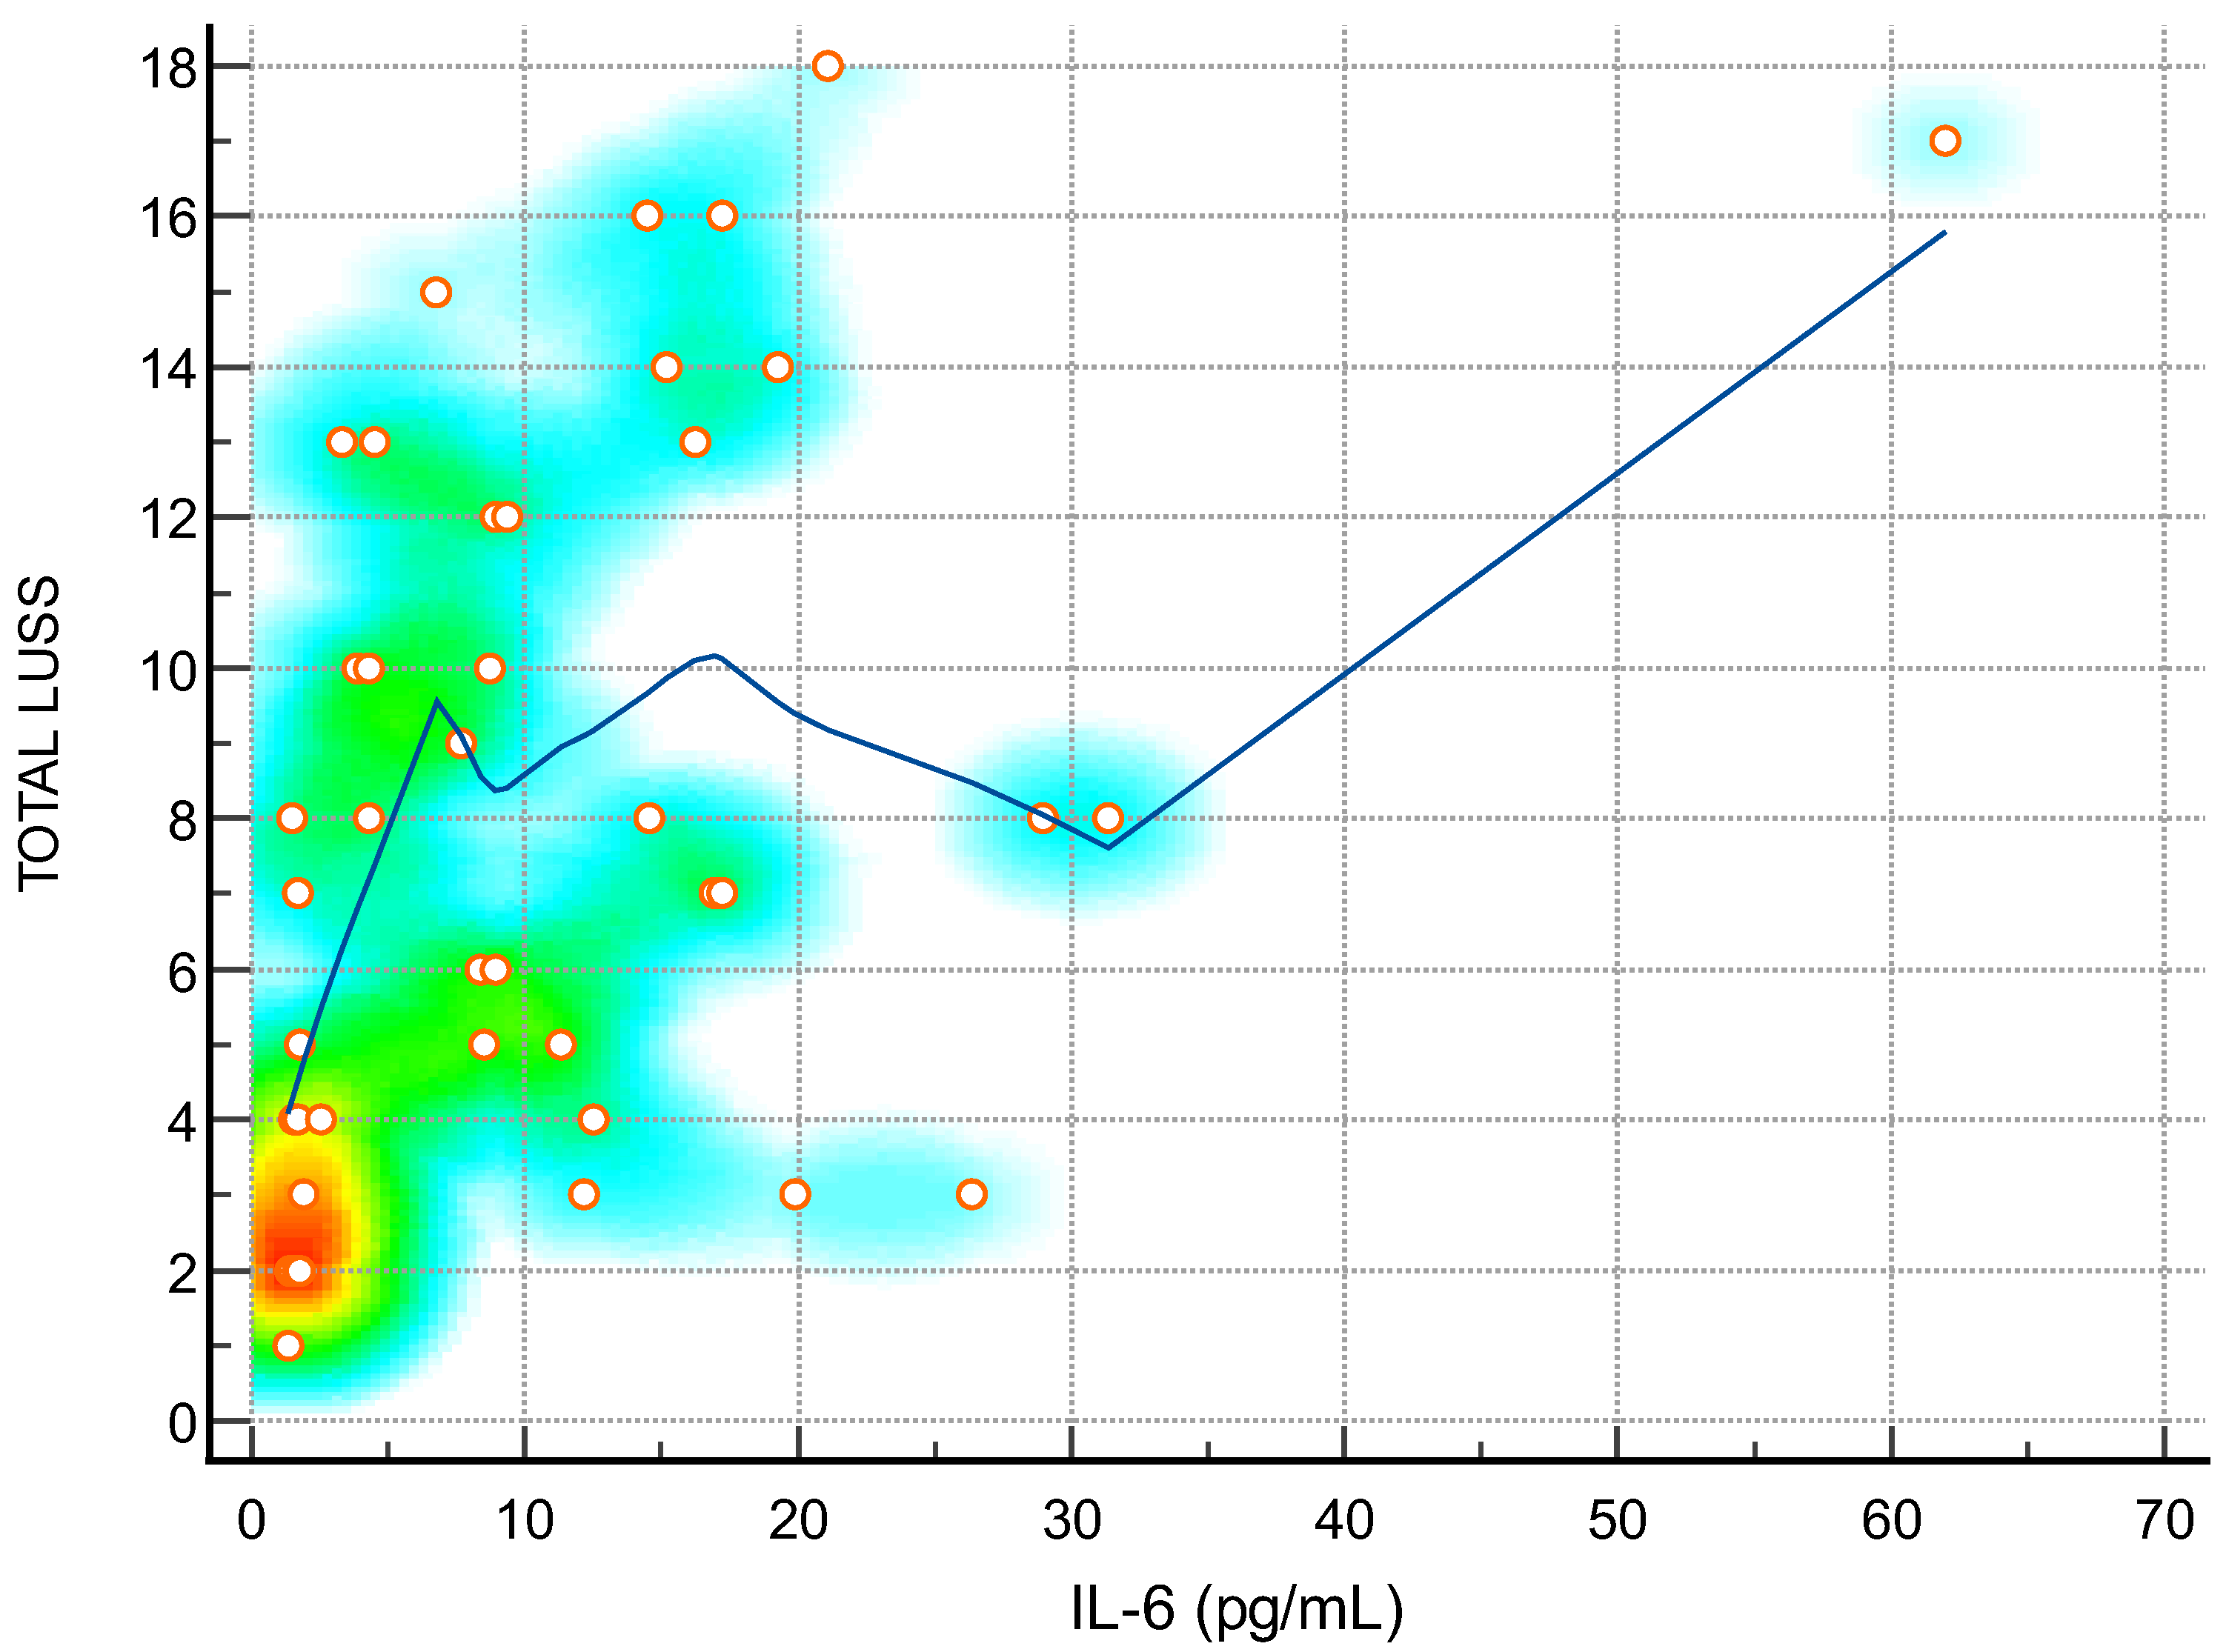

| IL-6 (pg/mL)—Figure 4 | 0.46 | 0.19 to 0.67 | 0.0017 |

3.4. Lung Ultrasound Score and Correlation with Inflammatory Markers